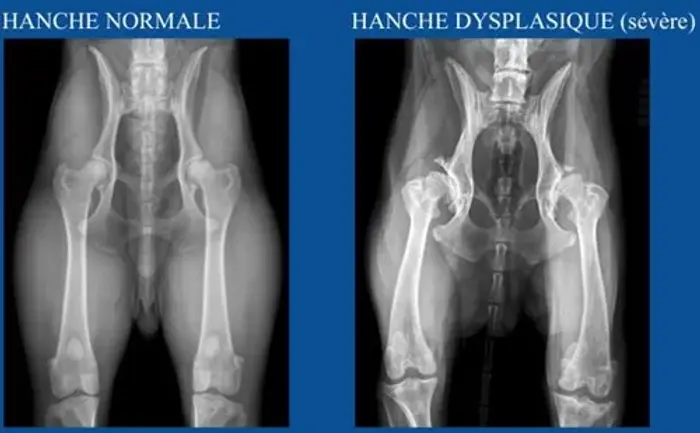

Dysplasie hanches et coudes

La dysplasie des hanches et des coudes se testent grâce à une radio des hanches et des coudes effectuée après les 1 an du chien. Ces radios sont ensuite envoyées à des examinateurs officiels qui jugent et donnent une note allant de A à E pour les hanches et de 0 à 3 pour les coudes.

HD-A: aucun signe de dysplasie (peut reproduire)

HD-B: état presque normal (peut reproduire)

HD-C: dysplasie légère (peut reproduire qu'avec du A)

HD-D: dysplasie moyenne (ne doit pas reproduire)

HD-E: dysplasie sévère (ne doit pas reproduire)

Ci-dessous des exemples trouvés sur internet